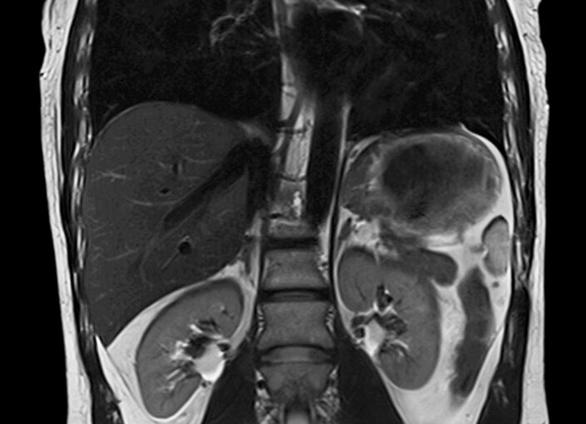

Снимок МРТ брюшной полости

Часто МРТ брюшной полости проводят в комплексе с процедурой обследования органов и полостей забрюшинного пространства. В этом случае затрагиваются также почки с надпочечниками, благодаря чему с высокой степенью точности проводится выявление опухолевых и иных образований, вторичных опухолей, а также патологических состояний, аномалий и травматических последствий для всей брюшной полости и забрюшинного пространства.